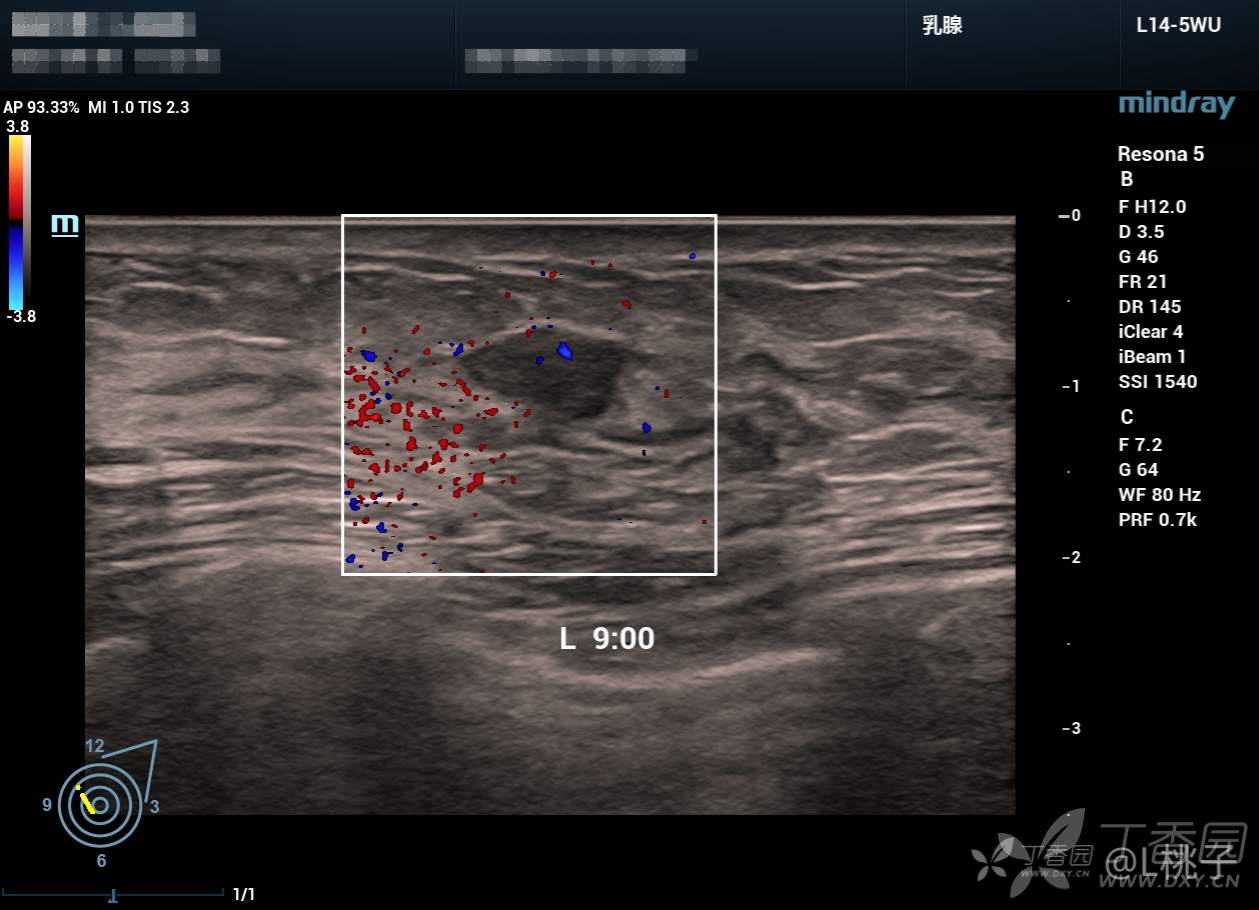

发部分乳腺结节的病例

大家考虑一下分级

病例1: